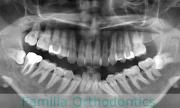

かみ合わせが悪い、顎が出ているのを治したいと来院されました。驚くことに、これまで小児期から成人にかけて3回も矯正治療を行っており、歯根吸収も著しい骨格性の受け口ということで、大変な難症例でした。2年半、30回程度の通院が必要でした。

外科的矯正治療には、矯正治療単独で行った場合のリスクや副作用に加えて、外科手術のもつリスクがあります。全身麻酔や入院の必要性、術後の疼痛や顔の腫れ、手術部位周囲の感覚麻痺などがそれにあたります。

厚生労働省のガイドラインを守るために書くのならば、この症例のリスクは前記のようになるでしょうが、このケースに関しては「骨格のズレを度外視?もしくは見逃し?して矯正治療を行うことのリスク」が最大限に表れていると言えるかもしれません。